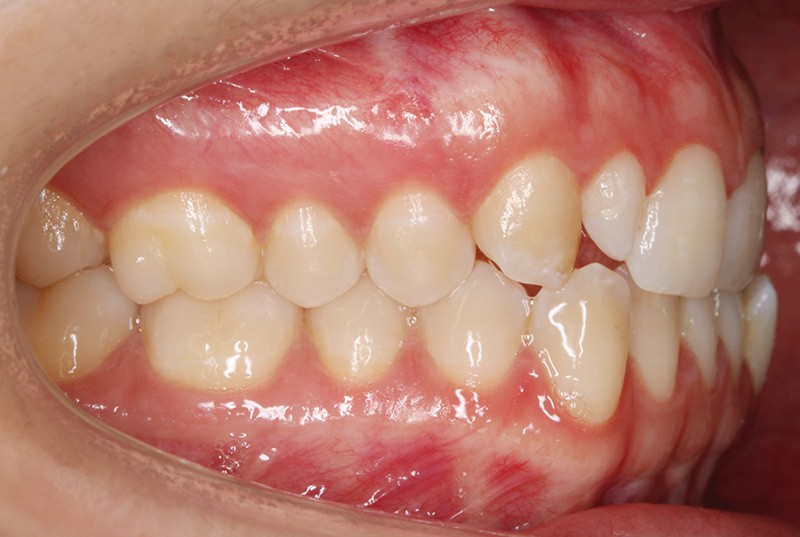

Elle présente une classe I dentaire en denture adulte. Son sourire est perturbé, notamment par la microdontie de son incisive latérale maxillaire droite (la 12). On constate un encombrement modéré au maxillaire (bimarginotopie mésio-palatine et disto-vestibulaire de 13) et plus marqué à la mandibule (monomarginotopie mésio-vestibulaire de 32 et de 43) (fig. 1-6).

Les milieux inter-incisifs ne sont pas coordonnés, à torts partagés, avec une légère déviation à droite du milieu inter-incisif maxillaire et une déviation plus marquée à gauche du milieu inter-incisif mandibulaire ainsi que du point menton. 32 et 33 présentent une tendance à l’exoclusion.